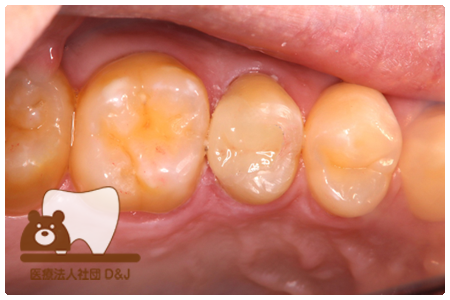

症例8フルジルコニアクラウン

治療前

治療中

治療後

29歳 女性

- 治療内容

- 銀歯からフルジルコニアクラウンへの修復

- 治療期間

- 根の治療含め3か月

- 費用

- 自費

フルジルコニアクラウン:77,000円(税込)

- その他の治療の費用は含まれておりません。

- リスク・副作用

- 強い衝撃が加わると欠けたり割れたりする可能性があります。また、噛み合わせの状態によっては脱離や周囲の歯への影響が出ることもあります。